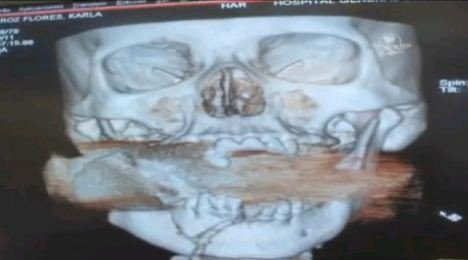

英國《每日郵報》9月有28日報道稱,育有三子的卡拉弗洛里斯生活在墨西哥錫那羅亞州的庫利亞坎。一天,正在街上販賣海鮮的她在聽到一聲巨響后,被一件物體擊倒。她感到臉上一陣熱,伸手摸到一灘血。隨即失去知覺的卡拉被送往醫院,醫生在為她進行X光掃描時發現,一顆未爆炸的手榴彈卡在卡拉的上頜骨與下頜骨之間。

醫院立刻提高了警覺。顯然,這個手榴彈在被手榴彈發射器發射后沒有爆炸,卻嵌入了卡拉頜骨正中。由于它隨時有爆炸危險,卡拉被隔離開來,醫院的病人及員工都被撤離。由于醫生都不愿意為卡拉動手術,最后醫院院長自愿來完成這個驚心動魄的手術,另外兩位麻醉師、一位醫生及一位護士為其充當助手。